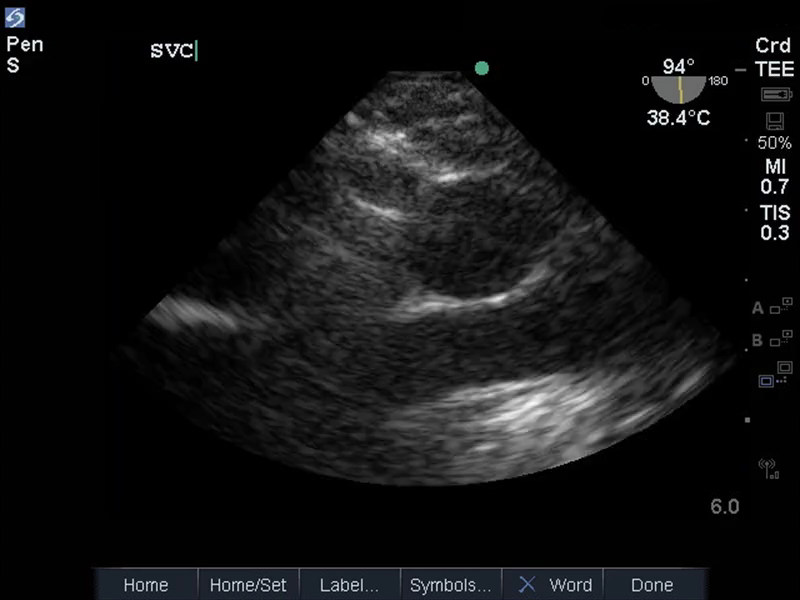

TEE 中段食管 SVC 图像